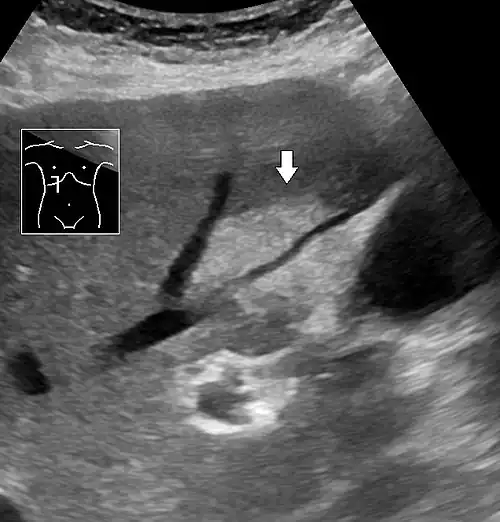

On X-ray computed tomography (CT), the increased fat component will decrease the density of the liver tissue, making the image less bright. Typically the density of the spleen and liver are roughly equivalent. In steatosis, there is a difference between the density and brightness of the two organs, with the liver appearing darker.[12] On ultrasound, fat is more echogenic (capable of reflecting sound waves). The combination of liver steatosis being dark on CT and bright on ultrasound is sometimes known as the flip flop sign.

On abdominal ultrasonography, steatosis is seen as a hyperechoic liver as compared to the normal kidney.